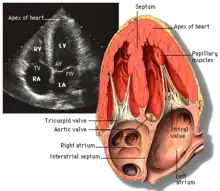

Apical four chamber (A4C)

This view is obtained at the apex of the heart and looking toward the base of the heart (where the valves are). In this view, the mitral valve, tricuspid valve, and all four chambers are visible. This view shows the right ventricle from base to apex and is a useful view to estimate RV systolic function. TAPSE (= tricuspid annular plane systolic excursion) is also measured in this view with M-mode through the lateral tricuspid annulus.

Structures:

- Inferior septum and anterior lateral segments of the left ventricle

- Right ventricle

- Left atrium

- Right atrium

- Mitral valve

- Tricuspid valve